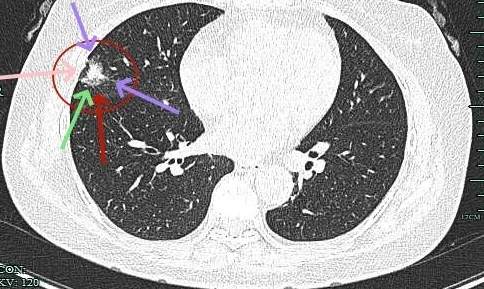

病灶大部分实性,边缘细毛刺与少许磨玻璃成分。

感觉整体病灶有膨胀性,边缘有毛刺征,灶内密度不是太致密。

叶间胸膜受牵拉凹陷,有微小血管进入,表面毛刺与不平。

实性成分也有明显毛刺,叶间裂牵拉明显,表面有分叶征。